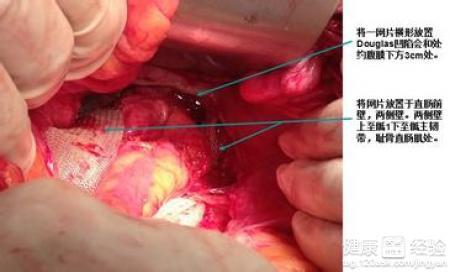

子宫脱垂手术